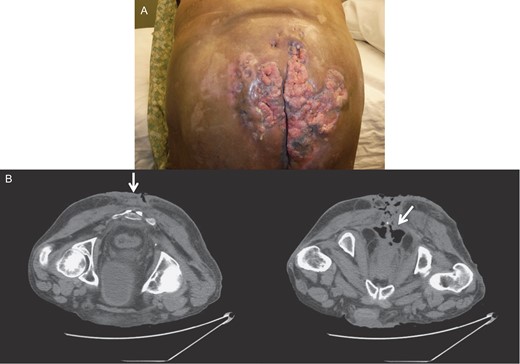

While neoadjuvant chemoradiotherapy, with 5-fluorouracil, mitomycin-C and radiation dose of 45 Gy, at pelvic, perianal and gluteal regions was started, the patient was lost in follow-up. He was readmitted 2 months later for trouble controlling bowels, for which he underwent diverting colostomy. There was significant necrosis of the tumor (Fig. 2), and the biopsy showed with mild to moderate dysplasia. A wide local excision and debridement of the soft tissue were performed down to presacral fascia and gluteal fascia on right and left buttocks.

Gross image (A) and CT of the pelvis and perineum (B) showing exacerbation of the tumor with significant necrosis and invasion into the rectum and anal canal.